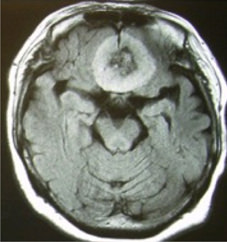

神経膠芽腫のMRI

白くうつっているところが腫瘍ですが、その周囲にも腫瘍細胞が染み出すように増殖しています。